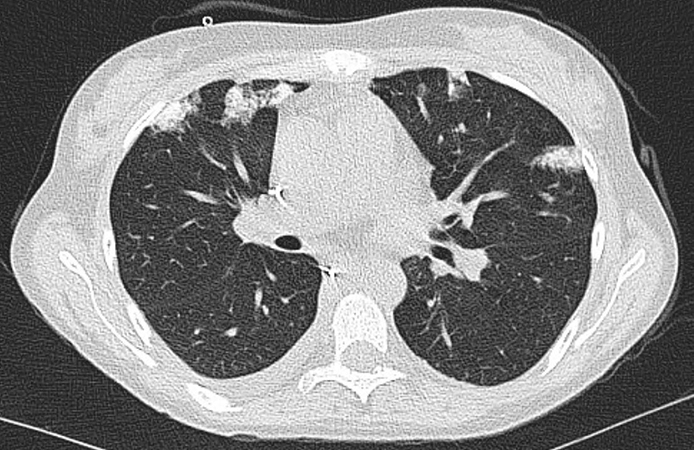

A dedicated thoracic CT scan demonstrated multifocal bilateral consolidations with anterior predominance (Figure 1) without evidence of pulmonary embolism. Blood tests were significant for anemia, and CMV, EBV, and coronavirus screening tests were negative. The clinical differential diagnosis included organizing pneumonia, post-transplant lymphoproliferative disorder, and atypical infection in the setting of immunosuppression. A transthoracic biopsy was performed. Representive images are shown in Figures 2, 3 and 4 (H&E) and Figure 5 (HPS). No microorganisms were detected on special stains.